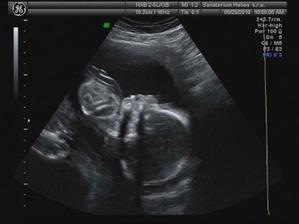

UTZ ve 20 tt 8.6. - odpovídáme 21+1 tt (trošku jsme vyrostli), vše v pořádku a mimi váží 400 g 😉